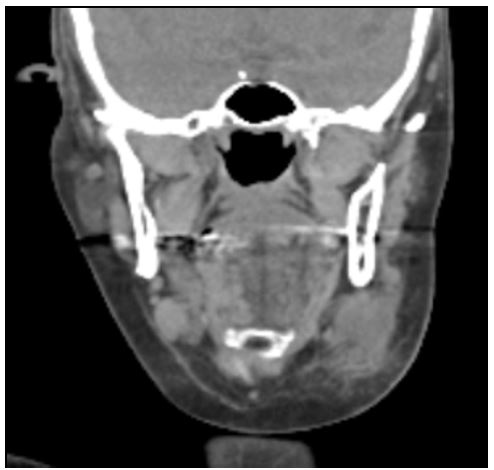

The nine-month period was ended by a low velocity, blunt force trauma against the left side of the neck, leading to increasing pain and swelling, prompting clindamycin treatment by the general practitioner. A subsequent CT-scan showed a submandibular collection with a superficial and deep component, accompanied by additional infiltration of the subcutaneous adipose tissue, focal skin thickening and lymph node enlargement (Figure 2).

Figure 2: Coronal section of the CT-scan after the clinical stable period showing a left sided submandibular collection with a superficial and deep component, with infiltration of subcutaneous adipose tissue.